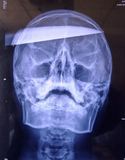

Het mes heeft bijna het hele hoofd van de jongen doorboort en steekt net niet aan de andere kant van zijn schedel er weer uit. De jongen was nog bij bewustzijn en werd snel naar het dichtstbijzijnde ziekenhuis gebracht. Na een operatie van 10 uur is het mes succesvol uit het hoofd van de jongen verwijderd, maar hij wordt nog geobserveerd voor het geval er deeltjes roest van het mes zijn afgekomen.

Volgens de doktoren heeft de jongen heel veel geluk gehad, omdat het mes de meeste belangrijke delen van de hersenen heeft gemist. Het internetcafé waar het incident plaatsvond is populair bij jongeren omdat er niet om identificatie gevraagd wordt. De volgende foto van de operatie kan als schokkend ervaren worden.